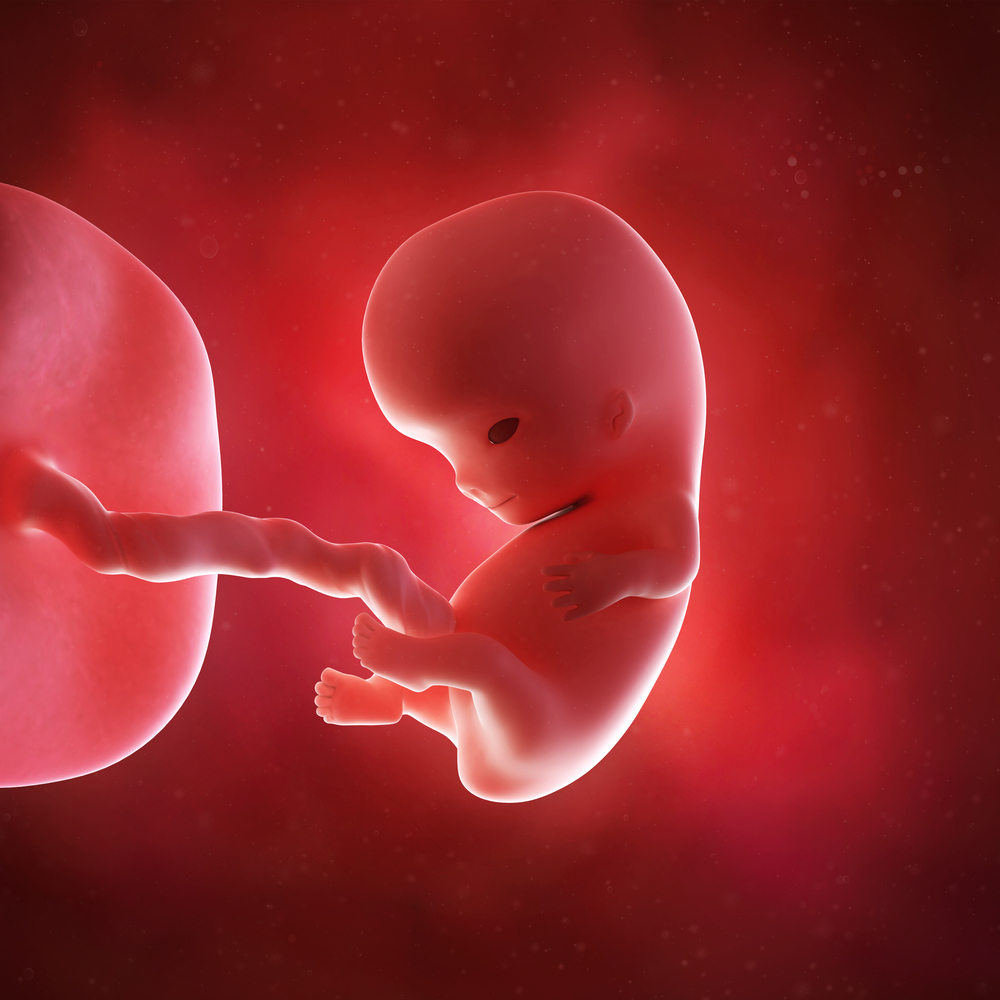

Your baby is undergoing a transition from an embryo to the fetal stage at 9 weeks pregnant. Your baby grows rapidly at the 9th week of pregnancy, i.e. limb and organ development occur at this stage. You can also hear the heartbeat of your baby with the help of a Doppler device.